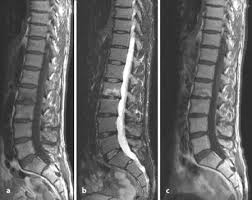

Figure 3 Magnetresonanztomographie Springerlink